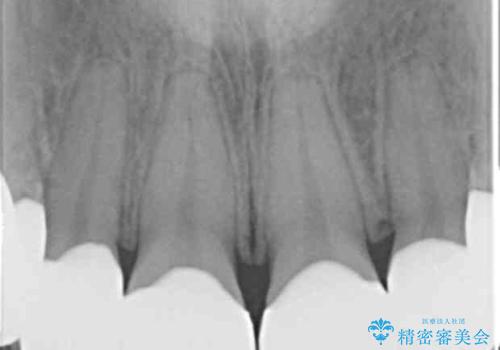

- K-POP(Kポップ)アイドルのような歯にしたいと希望され来院された患者様です。

矯正を途中でやめてしまったとのことで、歯に矯正の接着材が残っており着色も顕著でした。

奥歯の咬合面にはレジンが盛られた状態でした。

見た目と咬み合わせを改善するため、セラミッククラウンによる治療を行いました。

クラウンの種類:オールセラミッククラウン スタンダード